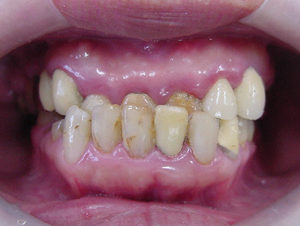

30代女性の患者様の矯正&審美症例です。 見た目を美しくしたい!早くホワイトニングをやってセラミックを入れたい!だけどなぜその前に矯正なのでしょうか? 歯並びが悪いことは見た目の問題だけではなく、お口の中の清掃状態が保て […]

悪くなってしまった歯だけを治すのではなく、お口の中全体の機能性を重視して、全体の審美性を高めた治療例をご紹介させていただきます。 この患者様は過去に交通事故で前歯を損傷し、それから10年以上にわたって歯茎の色と歯の色を気 […]